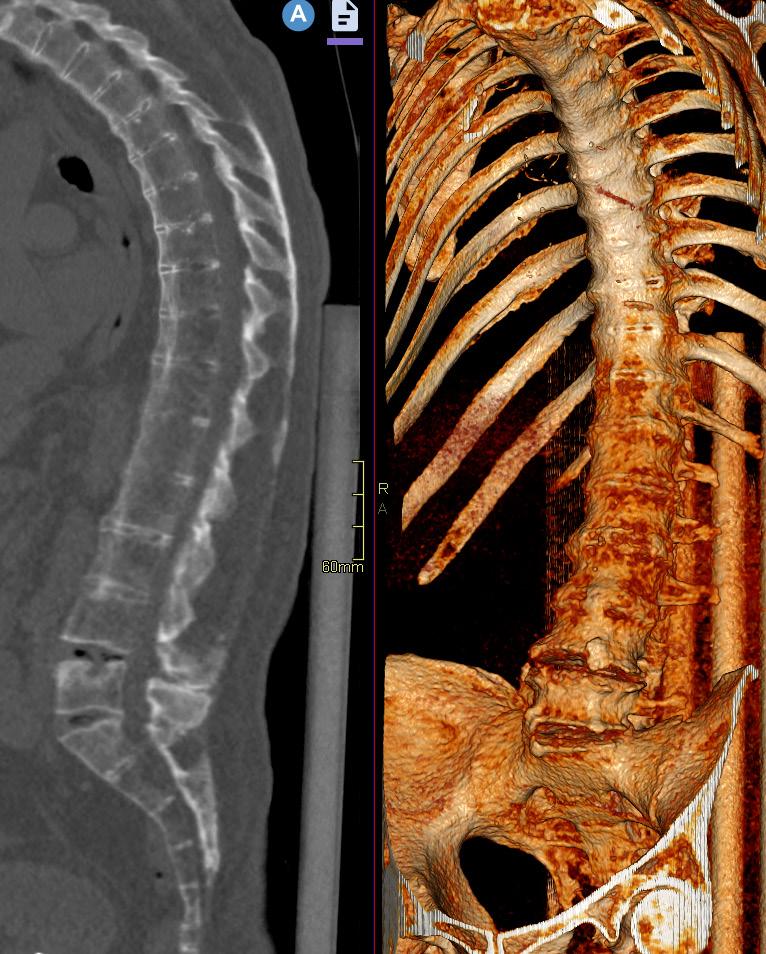

Bild 3. Lågdos-CT av en äldre patient med långdragen ankyloserande spondylit med ankylos i kotpelare och sacroiliacaleder. Sagittal reformatering och 3D-rekonstruktion. Bild 4. Cone-beam-CT med stol för patienten och vinklat gantry. Foto Mats Geijer.